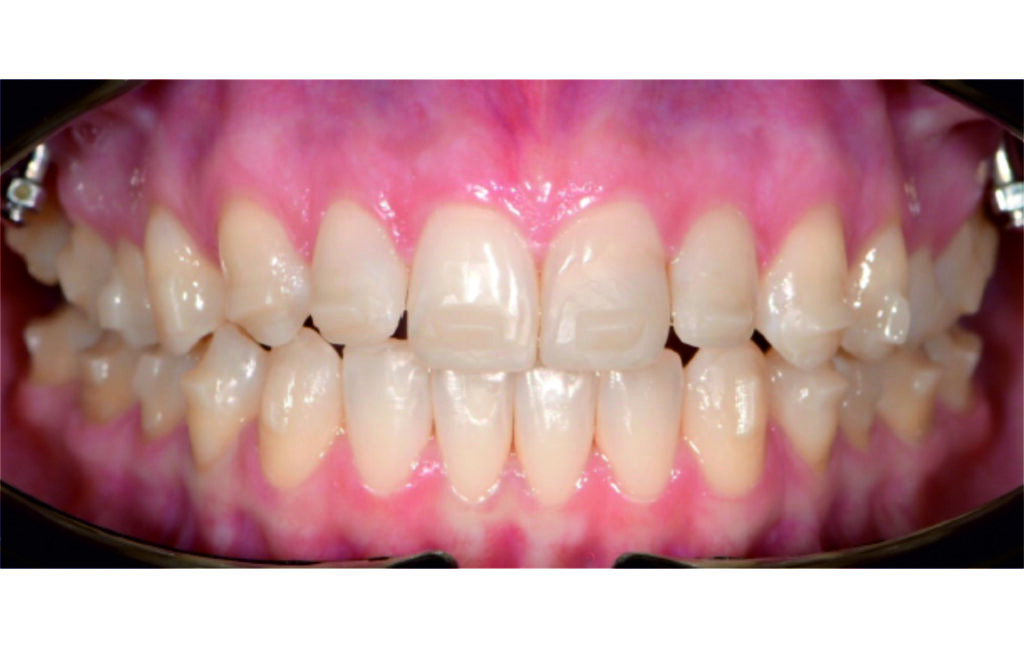

Angle Class II 2mm on the right, Angle Class II 2mm on the left, light mandibular asymmetry to the right, lower central line 1mm to the right, upper central line 1,5mm to the left, 1mm overjet and overbite. Sagittal asymmetry of upper dental arch. Light crowding upper and lower frontal segments, severe attrition of posterior teeth, night bruxism. Normal sagittal position of both jaws, high angle case, steep mandibular ramus,excessive lower facial height, open bite tendency.

The case initially presented as a moderate Class II on the right and a Class II tendency on the left, with tapered dental arches and an anterior open bite extending to tooth 26 in segment II.

A 1.5 mm deviation of the upper dental midline to the patient’s left was noted, along with a slight mandibular midline shift to the right, likely due to asymmetrical mandibular growth observed in the facial structure. Severe mesial rotations of teeth 16 and 26 were evident in the initial records. As derotation of 16, 26, 17, and 27 progressed up to aligner 16, the premolars in segments I and II moved distally, resulting in a bilateral Class I relationship, as intended in the initial treatment plan.

Derotation of 16 26 allowed Class II correction.

Vertical vector of elastic traction on buttons and IZC helped with the open bite correction.